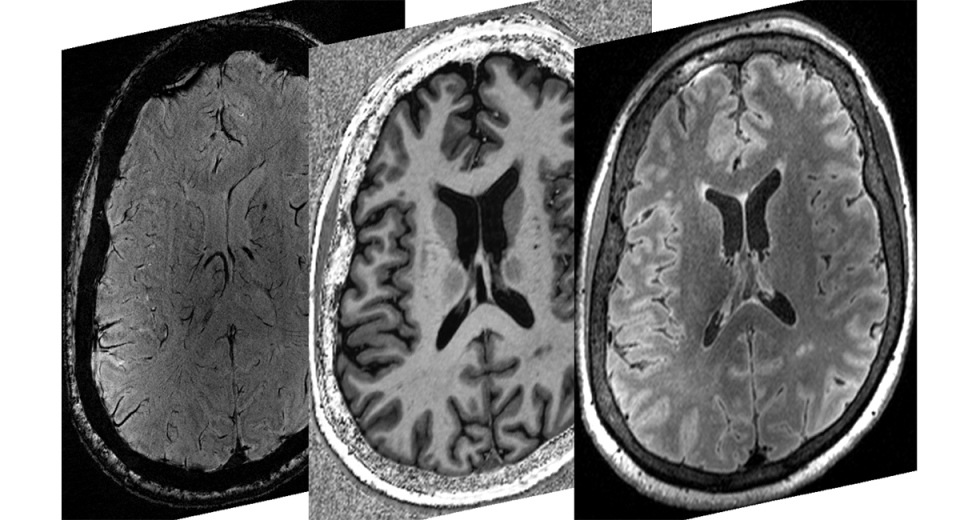

CFMM is grateful for the $16 million commitment by Western allowing us to acquire a new whole-body 7T high-field magnetic resonance imaging scanner (MRI), which produces ultrafine image resolution, is the latest in cutting-edge equipment to enhance Western’s leadership in neuroimaging research. This 7T scanner will offer up to 10 times higher resolution than standard 3T MRIs to detect microstructural abnormalities in the brain and throughout the body.

Dr. Corey Baron from the University of Western Ontario works to improve the understanding and diagnosis of neurological diseases. His lab focuses on developing and applying novel diffusion MRI techniques that probe tissue microstructure changes present in many pathologies, in addition to providing insight into the structure and function of the brain.

High-resolution images provide ‘unprecedented detail’ for study of brain structure & activity

Corey Baron, PhD, Canada Research Chair (Tier 2) in Diffusion Magnetic Resonance Imaging, is developing imaging biomarkers for ultra-high field MRI to learn more about the brain and improve disease diagnosis.